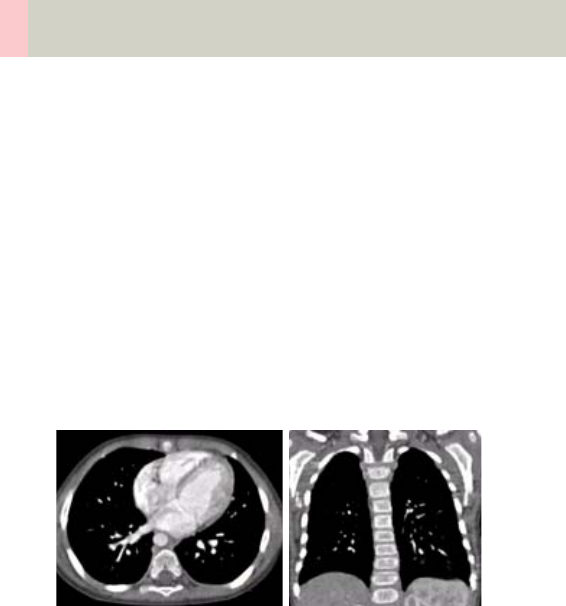

- Thorax

- ThoraxRoutine/ ThoraxRoutine06s

- ThoraxCombi/ ThoraxCombi06s

Thorax 226

•Overview 226

- General Hints 229

- Body Kernels 231

•Scan Protocols 232

- ThoraxRoutine/

ThoraxRoutine06s 232

- ThoraxCombi/

ThoraxCombi06s 235

- ThoraxVol 240